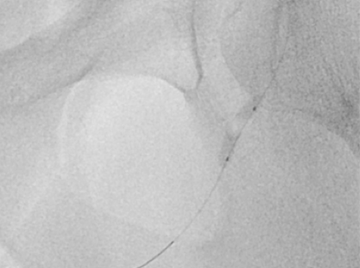

Die Stentbehandlung der Penisarterien ist keine Operation, sondern ein minimal-invasiver Eingriff. Bei örtlicher Betäubung wird ein kleiner Schnitt in der Leiste gesetzt. Über diesen Zugang wird ein sehr feiner Hohlschlauch (Katheter) über die Beckenarterie (Beckenschlagader) bis zu den Penisarterien geführt. Über den Katheter wird die verengte Arterie mit einem Ballon geweitet. Anschließend wird eine Gefäßstütze (Stent) eingesetzt, um die Engstelle zu stabilisieren.